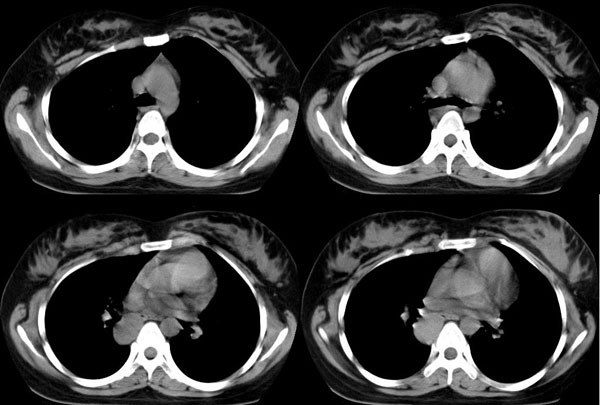

女,22岁,无明显症状

强化

后纵隔长条形囊性密度影,增强扫描似乎有强化。病灶与食道关系很密切,但在下方几个层面又显得有些疏远。

考虑:神经源性肿瘤,以神经鞘瘤可能大。

鉴别:1、支气管囊肿,太长了,增强扫描似乎有强化。

2、食管囊肿,增强扫描似乎有强化。

后纵隔食管右侧可见一囊性病灶,密度均匀,边缘光滑,未见钙化,与食管关系密切。无明显强化。

考虑食管囊肿。

首先定位在肺内。肿块最大径在右下肺叶后基底段,胸椎椎体右边偏后部。与气管、食管无关,如果是支气管或食管囊肿应该有细蒂与之连接。肿块边缘光整、密度均匀一致、轻度均匀强化。右主支气管轻度受压,右肺含气量降低,右胸腔略萎陷。

定性:右下肺良性肿瘤。